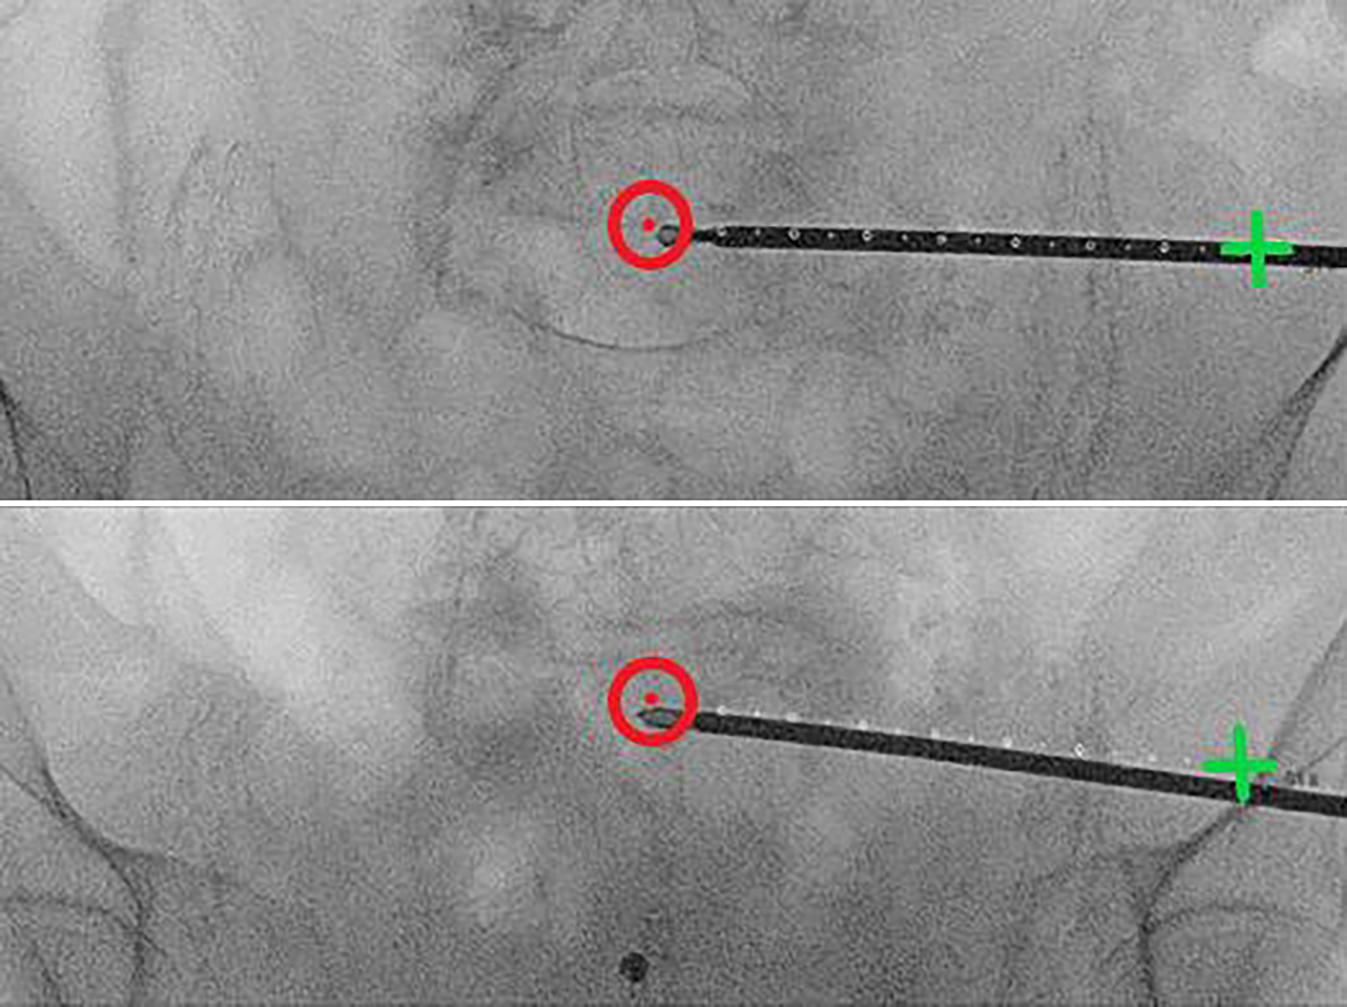

Fig. 6

Lateral fluoroscopic image with real-time projection of the planned guide-wire entry point (green cross), its direction (dotted line), and endpoint (red circle). The guidewire is positioned on the bone. Once correctly positioned, it is introduced into the bone via light mallet strikes until it penetrates three cortices. If the correct angle in the axial plane is achieved (usually 10–20°), the guidewire advances along the planned trajectory in the lateral view. The planned screw pathway is visible at all times on the fluoroscopic images, to allow for navigation and direct adjustment of the guidewire. To minimize the surgeon’s radiation exposure, the guidewire is held with a forceps

Fig. 7

The guidewire position is verified using the predefined personalized inlet and outlet angles (see appendix 2). While alternating between these personalized angles, the guidewire can be repositioned and driven into its final position with the drill. Key to this process is keeping in mind the vital landmark: the slightly S‑shaped anterior cortex of the S1 vertebral body. In uncertain scenarios, a higher dosage x‑ray may be acquired, or the contralateral side extrapolated for reference. Possible mismatch between diagnostic and intraoperative CT may result in an inaccurate planned screw pathway overlay; in such cases, the overlay can still provide an estimated guidewire pathway and end position. After final placement of the guidewire, its length is measured